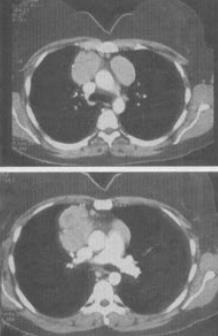

- 单项选择题 患者女,27岁,双侧颈部淋巴结肿大,PPD(-),结合CT图像,最可能的诊断是()。

- B